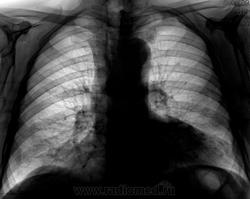

Не ясный...  В клинике превалирует одышка...

Более контрастные изображения.

Отмечает внезапно возникшую одышку? ЭХО-КГ было? Мне чудится симптом Вестермарка в верхней доле справа и нежная интерстициальная инфильтрация в S6 справа. Хвост правого корня не красивый, может он "обрублен"? Ну и признаки ХОБЛ есть.

Тень сердца объясняет причину одышки.

Коллеги, а как Вы объясните эту тень? Что-то я на ней зависла. Не ателектаз, не междолевой плеврит. Абдоминомедиастинальная липома?

Тень это жир, по прямому тоже хорошо видно что сердце жирновато

Попробую объяснить. Стрелок на картинках не нарисую, по причине что я сейчас однорукая (отдыхаю на больничном со сломаной правой). Я не настаиваю на своем мнении, мне только "почудилось". Если сравнивать лег рисунок верхних долей, то справа он мне кажется обедненным. Для такого-то сердца и сосудов по лег полям должно быть поболее. А интерстиц инфильтрация, потому что нет "пятен" и "хлопьев" сливающейся альвелярной (простите КТ-шный термин), а есть нежное сетчатое затемнение, на фоне которого прослеж сосуды. Вот дисковидных коллапсов я не нашла, покажете?

Насчет ХОБЛ - стенки бронхов утолщены муфтой, хрящевые кольца трахеи, главных, долевых и устьев сегментарных кальцинированы, это отлично видно на линейках.

У такого человека в возрасте мне кажется сейчас важнее всего как раз исключить ТЭЛА, ХОБЛ и застой это меньшее из зол.

А что это еще может быть? Может, на плевре, но по прямому снимку не похоже. Жировая подушка, я считаю, тем более пациент судя по всему не худенький

Как-то сомневаюсь я в абдоминомедиастинальной липоме. Огроменные размеры, фестончатый контур. Подумала ещё о парастернальной диафрагмальной грыже. Валентин Львович, а в архиве что?